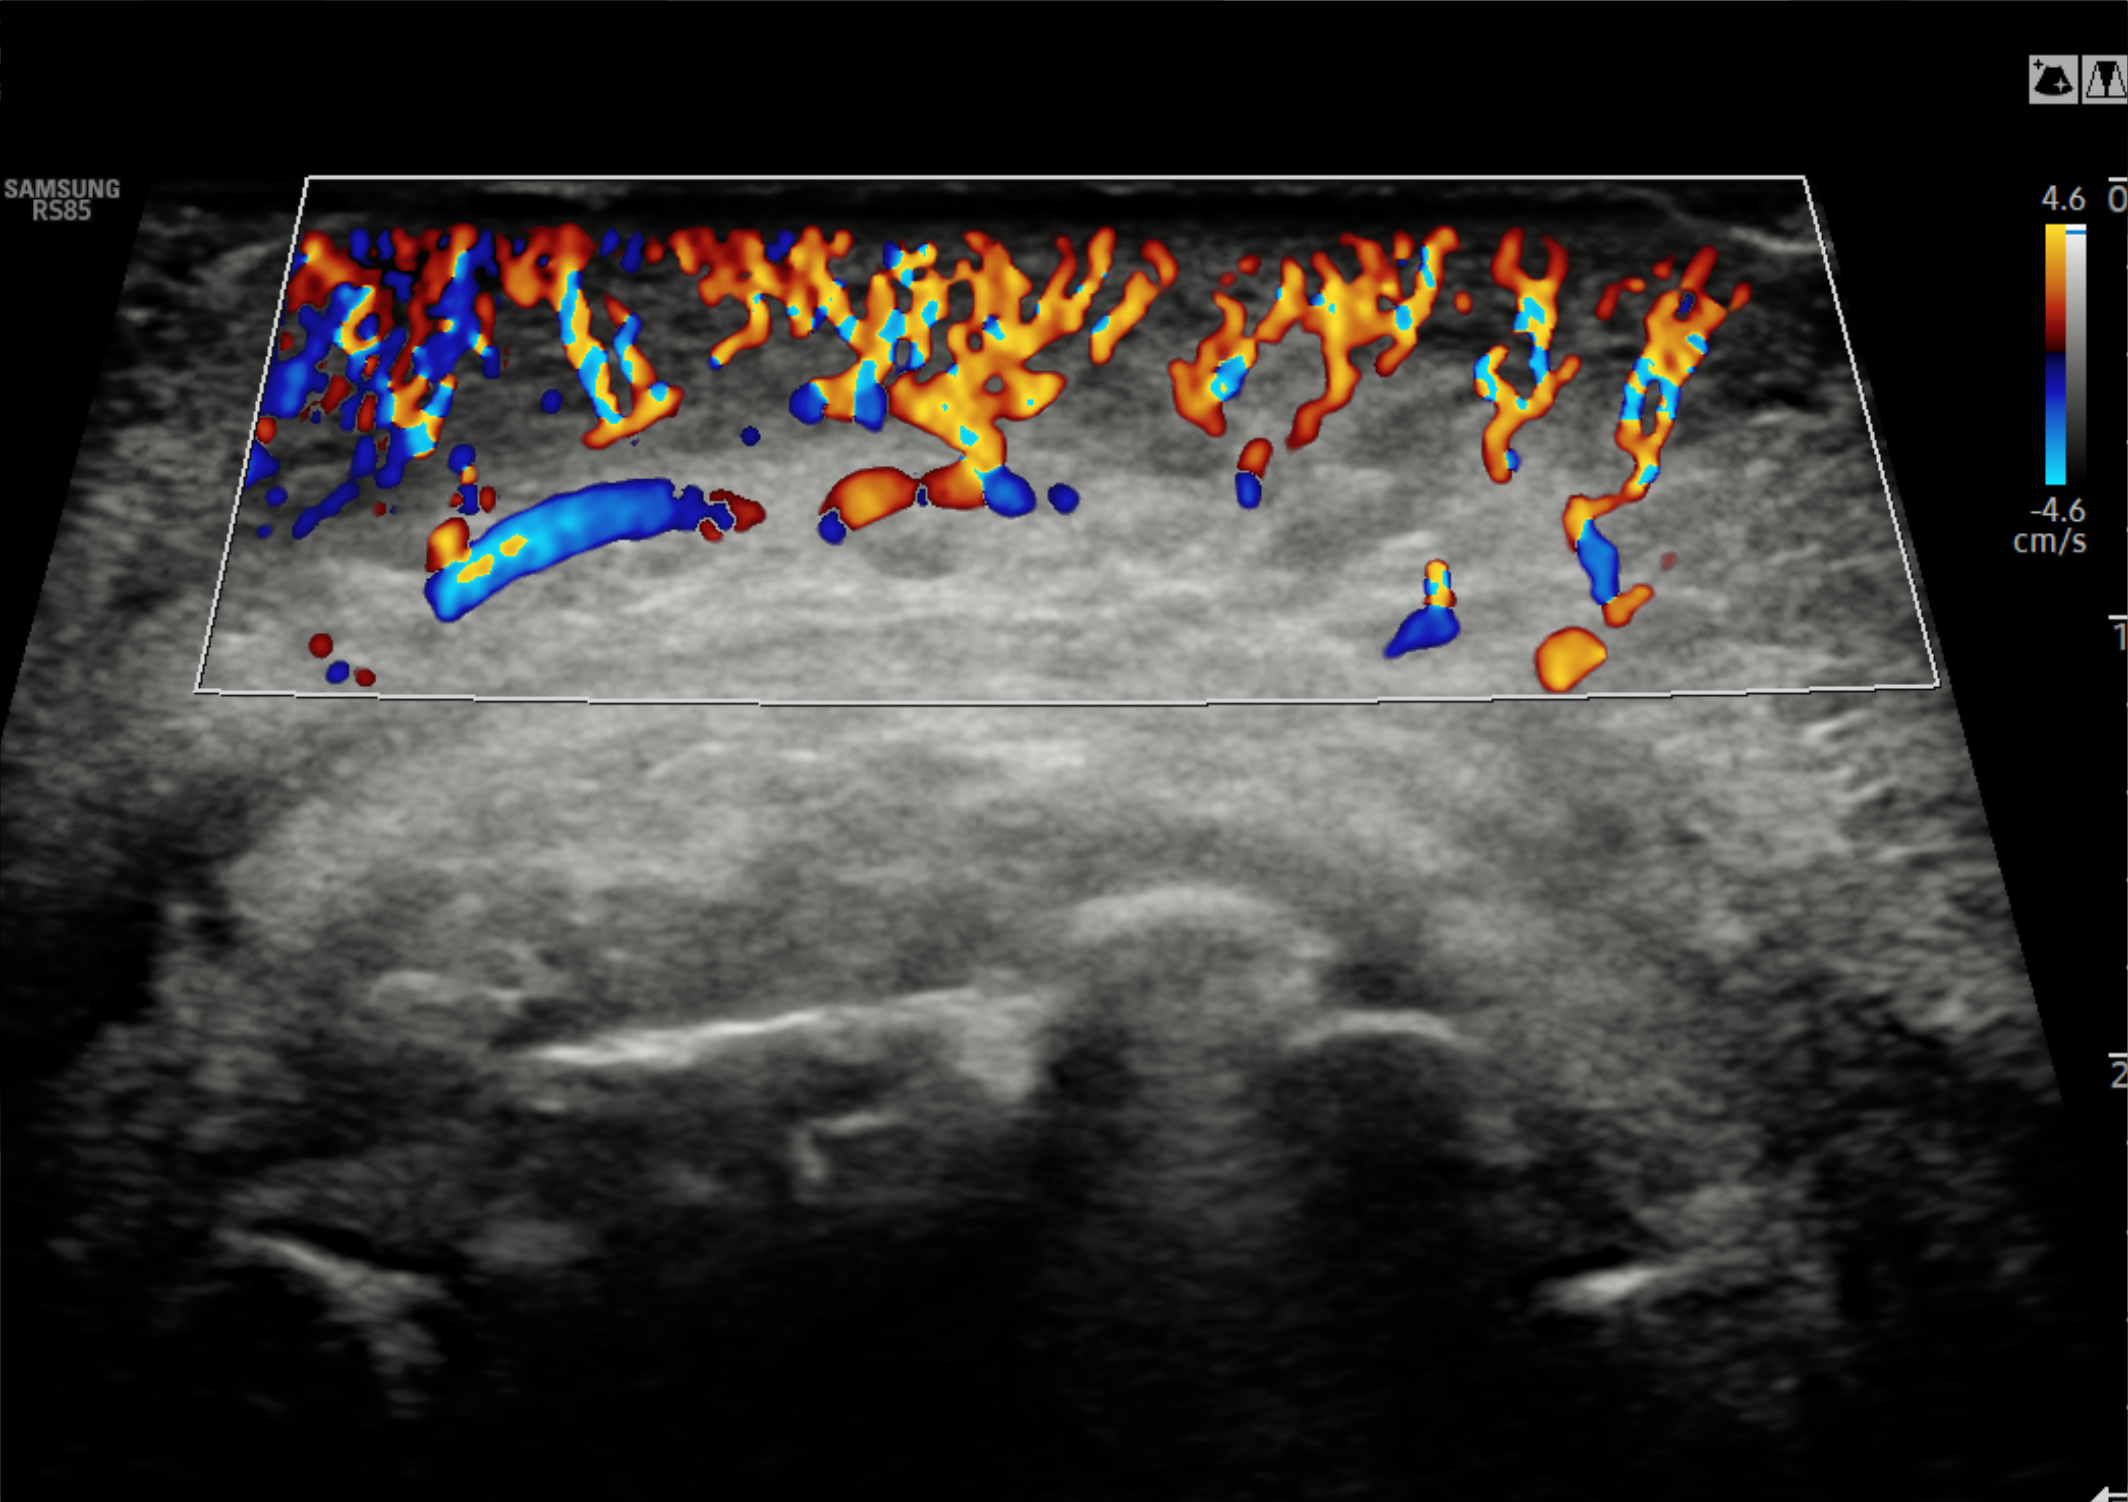

En Diagnoimagen incorporamos un enfoque de ecografía multiparamétrica, combinando modo B, Doppler color, Doppler de microflujo y elastografía, lo que nos permite una evaluación más completa y precisa en múltiples patologías.

🔹La ecografía Doppler permite evaluar el flujo sanguíneo en arterias y venas, siendo fundamental para el diagnóstico de insuficiencia venosa, várices, trombosis, estenosis carotídea y patología hepática.